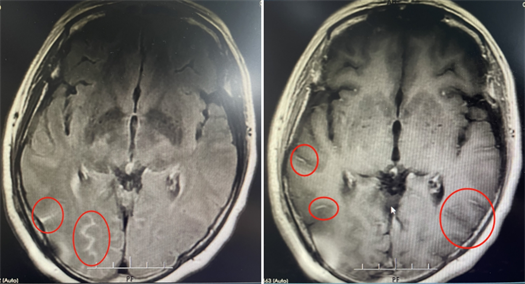

该院神经内一科副主任匡祖颖接诊后,怀疑患者是脑膜炎的可能性较大。最终通过腰穿检查在患者的脑脊液涂片中发现了隐球菌,从而确诊为隐球菌脑膜炎。

影像资料

尽管立即采用了抗真菌等对因治疗,但患者在住院期间还是出现了左眼视力下降,连光感都丧失了。复查腰椎穿刺发现脑脊液压力增高,提示颅高压。为避免长期高颅压导致头痛及颅神经损伤,匡祖颖安排患者转入神经外科行脑室腹腔分流术。